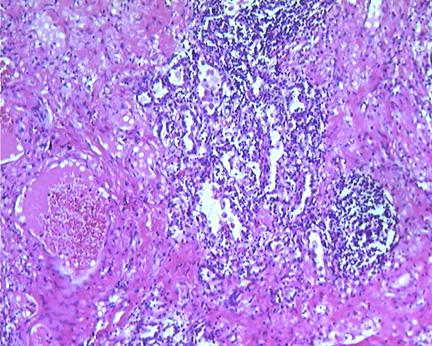

胸腔积液患者中,5%-10%患者积液发生感染并且嗜中性粒细胞聚积。如下图所示,这种炎症反应也会导致趋化因子、细胞因子、氧化剂和蛋白酶调解因子的产生。

图2 肺脓肿的组织学表现为炎症反应(低倍镜)

图3 肺脓肿的组织学表现为密集的炎症反应(高倍镜)